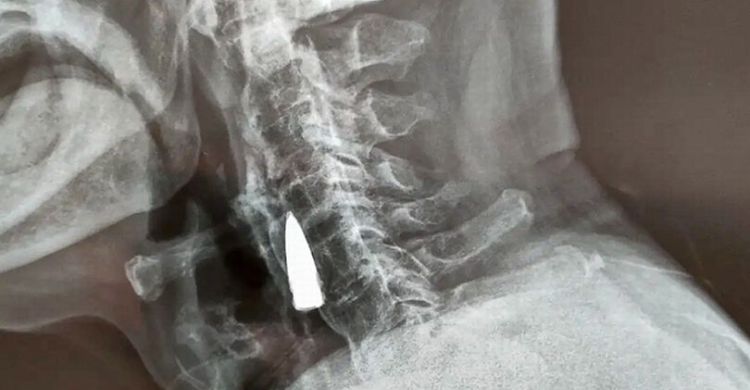

jaringberita.com - Sungguh mengejutkan dan membuat geger. Gile, sebuah peluru bersarang di leher seorang veteran perang selama 77 tahun.

Peluru itu baru terungkap setelah tim dokter melakukan rontgen terhadap veteran perang tersebut.

Namun, dia sama sekali tak sadar ada peluru yang bersarang di lehernya. Untungnya, amunisi yang bersarang itu tidak berbahaya bagi kesehatannya.

Karenanya, kendati dia telah memeriksakan diri ke rumah sakit di Kota Shandong, China, tim dokter tidak mengangkat peluru tersebut. Karena, jika diangkat, risikonya malah besar, mengingat usianya sudah sepuh.